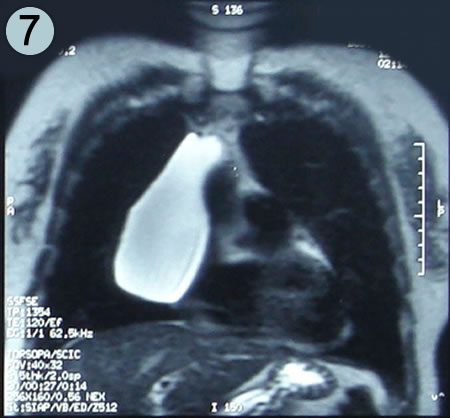

Resonancia Corte Coronal 7

Corte Coronal en Secuencia T2

La misma imagen o corte superior número 5, en secuencia T2, demuestra que la lesión es de contenido liquido por su aspecto brillante